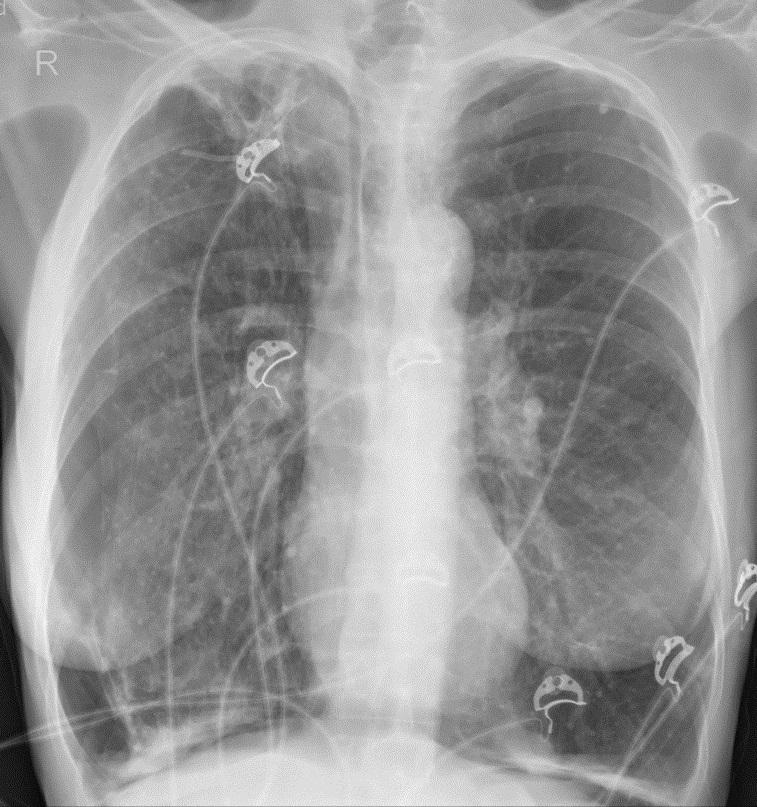

Röntgenfoto van een ribbenkast.

Een 54-jarige vrouw komt op de SEH vanwege plotselinge dyspneu en pijn aan rechterzijde van de thorax. In de voorgeschiedenis heeft zij onder meer een pneumothorax rechts en COPD. Ze heeft geen buikklachten. Bij lichamelijk onderzoek is er rechtszijdig verminderd ademgeruis. Het abdomen is soepel en niet drukpijnlijk, wel is er sprake van hypersonore percussie.